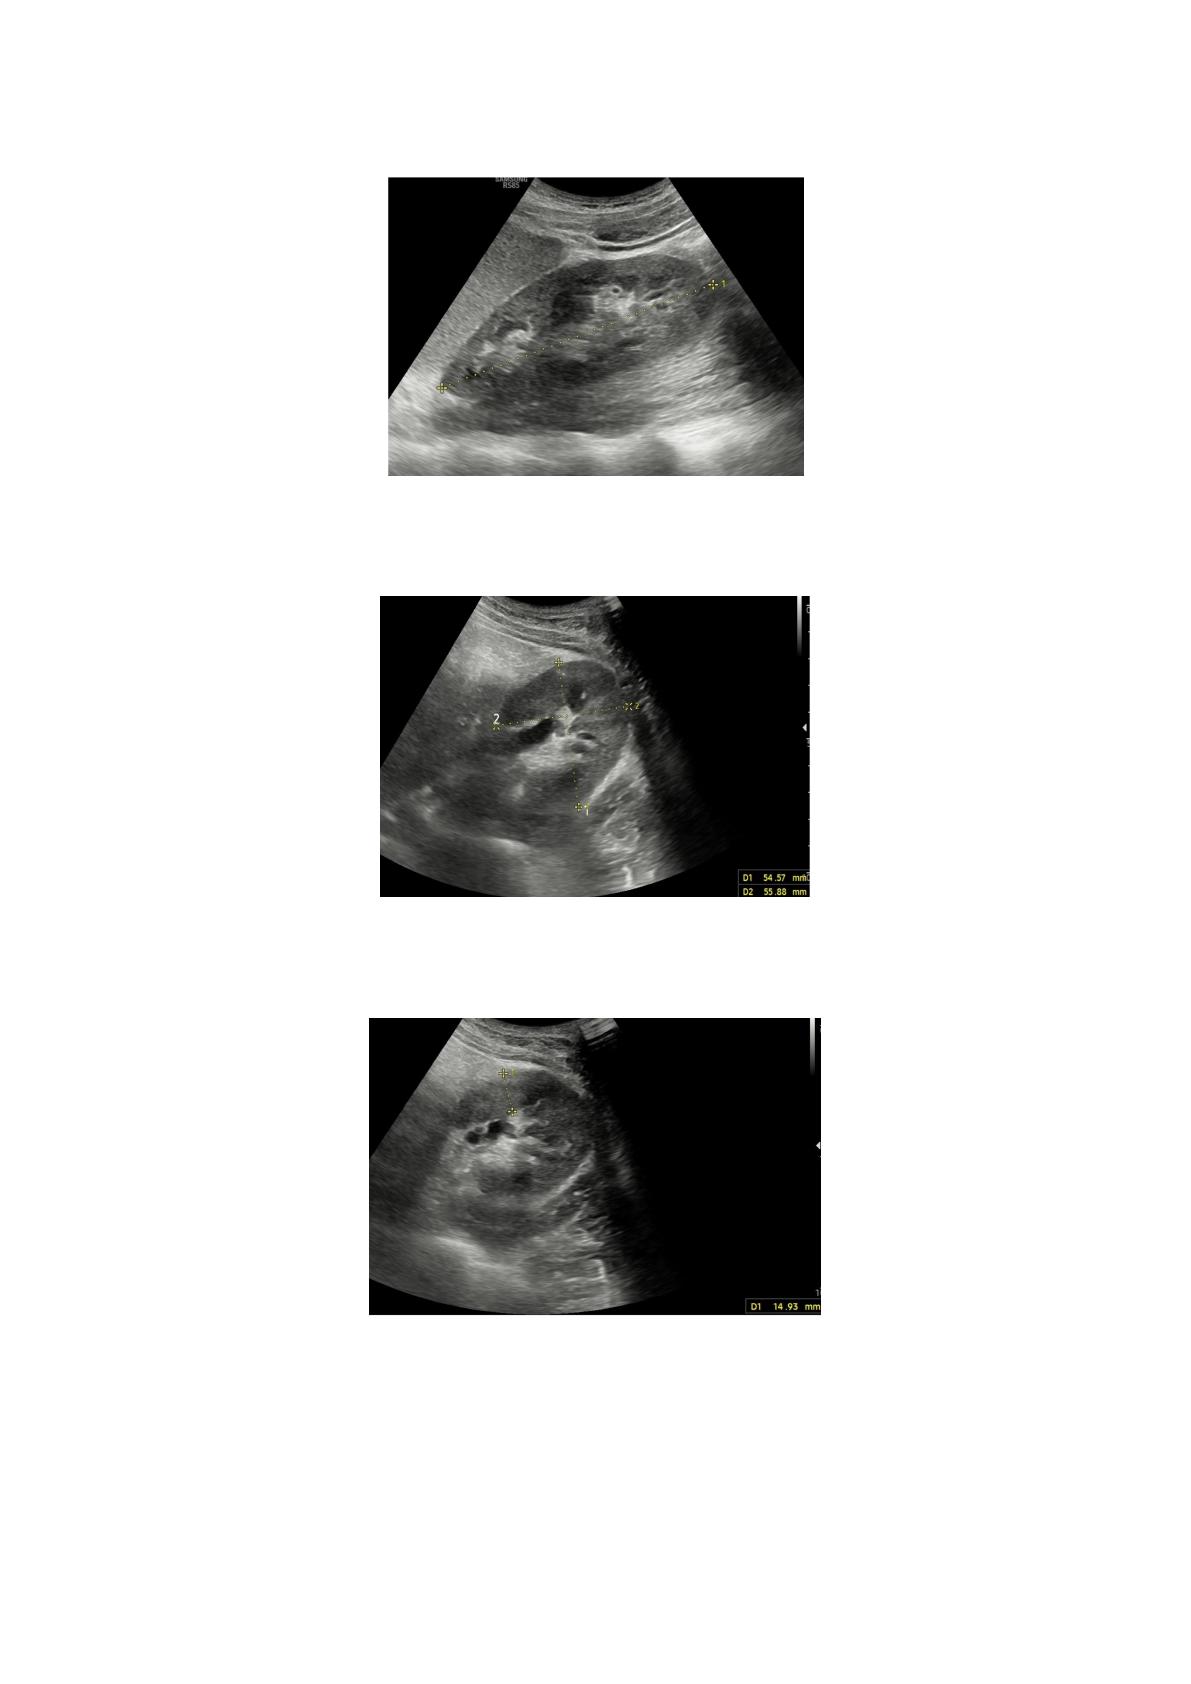

3. RÉSULTATS

Au total, 1918 patients ont été inclus dans cette étude. Parmi

eux, 987 (51,5 %) étaient des femmes et 931 (48,5 %) des hommes.

L'âge moyen des patients était de 40,74 ± 15,95 ans. L'IMC moyen des

patients était de 26,91 ± 5,11. Statistiques descriptives des régions

organiques où les mesures ont été prises.

Tableau 1. Statistiques descriptives des régions d’organes où les mesures ont été prises.

-Moyenne ± écart type Medyan (25e~75e)

ÂGE 40,74 ± 15,95 39,0 (26,0 ~ 54,0)

IMC 26,91 ± 5,11 26,23 (23,35 ~ 29,98)

LL 14,08 ± 1,49 14.2. (13.10 ~ 15.10)

LD 10,6 ± 1,2 10,6 (9,8 ~ 11,5)

SL 9,46 ± 1,4 9,6 (8,5 ~ 10,5)

ST 4,06 ± 0,73 3,9 (3,5 ~ 4,5)

RKL 10,72 ± 0,75 107,0 (10,2 ~ 11,2)

RK APT 4,94 ± 0,58 4,9 (4,5 ~ 5,3)